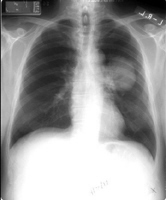

x-ray photo showing lung cancer

|